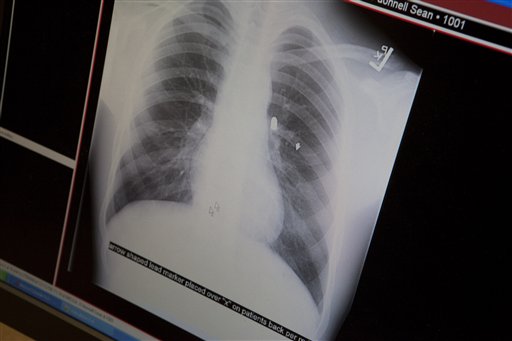

Οι γιατροί που τον εξέτασαν αποφάσισαν να πάρουν μία δύσκολη απόφαση. Καθώς δεν μπορούσαν να ρισκάρουν κανονική εγχείριση κατάφεραν να “εισχωρήσουν” ένα είδος μπαλώματος στην κομμένη αορτή. “Δεν το θεώρησα ιδιαίτερα ριψοκίνδυνο” αναφέρει ο χειρούργος Sean O’ Donnell, που λέει ότι αποφάσισε να χρησιμοποιήσει αυτή την πρωτοποριακή μέθοδο, καθώς βρήκε τον νεαρό σε ασυνήθιστα καλή κατάσταση.